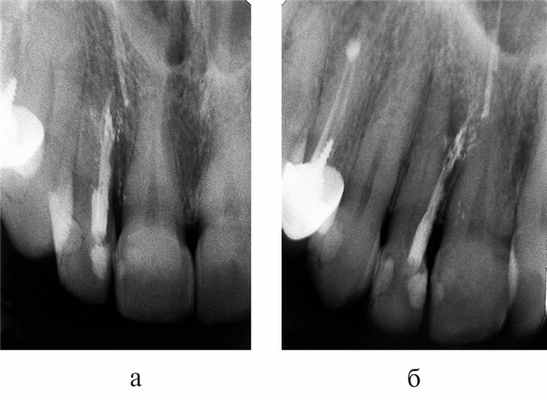

Важнейшими аспектами успешной внутриротовой радиографии являются стандартизация и последовательная коррекция манипуляций. Под стандартизацией манипуляций подразумевается способность специалиста, проводящего лучевое исследование, выбрать оптимальный для каждого случая метод и сделать серию идентичных снимков вне зависимости от положения, состояния пациента и времени, отделяющего одно исследование от другого. То есть, если диагностический или измерительный снимок признан качественным, каждый последующий уточняющий и контрольный должны быть сделаны с теми же пространственными и техническими установками и каждое последующее изображение должно быть идентично предыдущему (рис. 1, 2) .

Рис. 1. Диагностический и измерительный снимки зуба 36, выполненные в прямой (а) и дистально-эксцентрической проекции (б). 36 — хронический апикальный периодонтит (К04.5) с характерными изменениями на мезиальном корне.